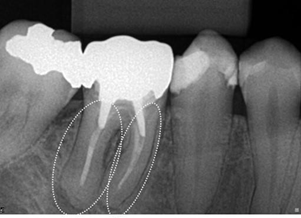

Figure 9 Panoramic X-ray cutout showing highlighted tooth 48, with some mesiangulation. Note that in iatrogenic endodontic treatment of the mesial root, one of the root canals is partially filled. This may be causing the space in the apical periodontal ligament to increase in that root .

Figure 10 Panoramic X-ray cutout showing highlighted tooth 46, with correct endodontic treatment and with a coarse excess on its mesial surface, that causes iatrogeny. As the tooth is dead, the patient will be slow to feel the symptoms of this iatrogeny, excess restoration, which will possibly destroy the tooth. Note that there is already a caries infiltration.

Figure 11 Panoramic X-ray cutout showing highlighted tooth 46, with iatrogenic endodontic treatment. There is a prosthetic crown with a fused metallic core with a larger support at the distal root. Note that in endodontic treatment there is a lack of material in both roots, and apical radiolucent images of these, partially diffuse, greater in the mesial root, compatible with apical lesion such as chronic abscess or granuloma. Both have a slow characteristic, due to the halo, or condensing osteitis that has formed around the lesions. Tooth 45 also has an endodontic treatment, but it is correct.